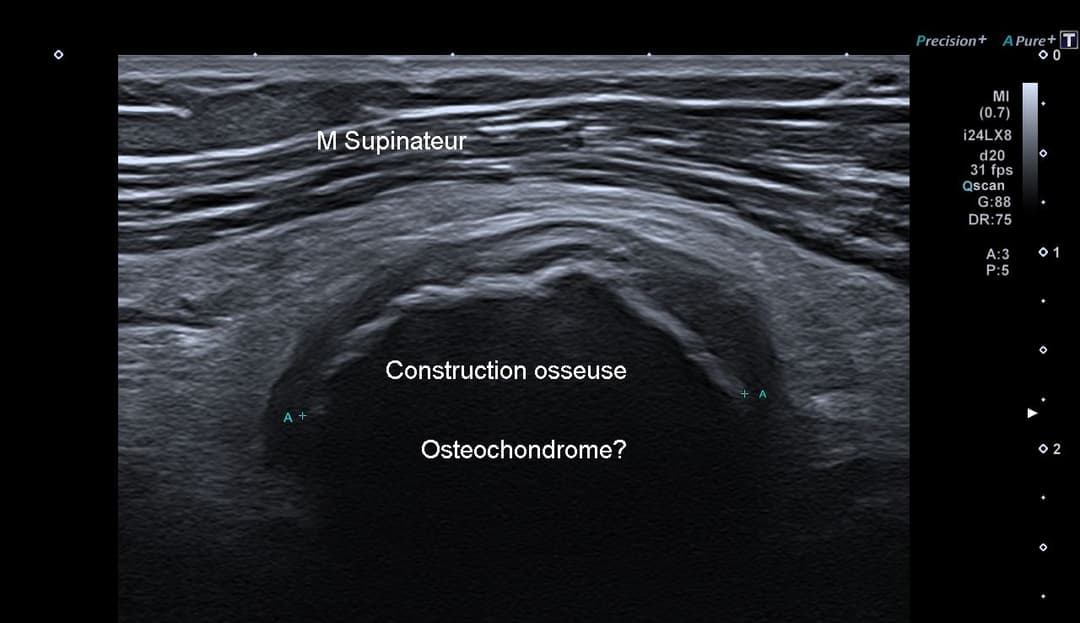

Échographie

Volumineuse structure osseuse additionnel qui s'avérera être un ostéochondrome de la tête radiale.